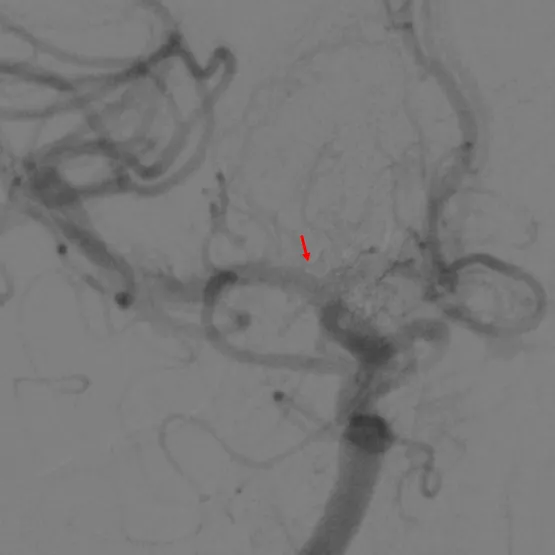

经右眼动脉入路工作角度

经右眼动脉工作路径

SONIC微导管路径

SONIC微导管到位后手推造影确认

注胶

确认瘘口消失-右侧

确认瘘口消失-左侧

SONIC微导管到位较深,注胶时可采用楔入技术,Onyx胶基本未反流,头端无粘管, SONIC微导管头端未解脱即顺利拔管